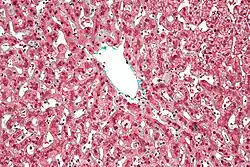

| Micrograph of congestive hepatopathy demonstrating perisinusoidal fibrosis and centrilobular (zone III) sinusoidal dilation. Liver biopsy. Trichrome stain. | |